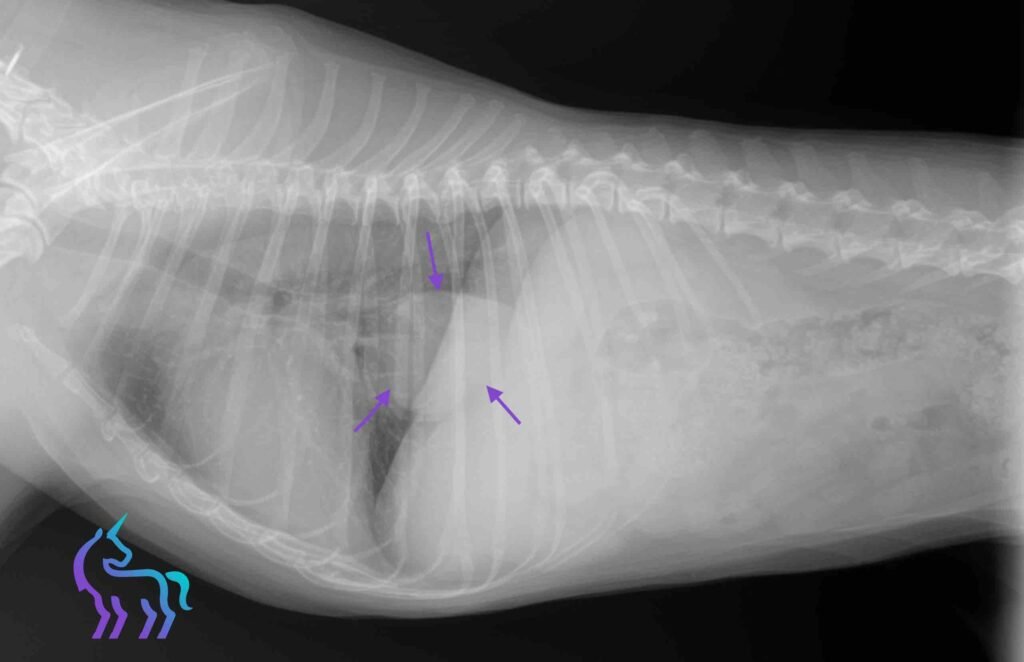

À découvrir : L’imagerie au service du diagnostic – nos cas cliniques L’Équipe des Licornes Cas cliniques en radiographie vétérinaire